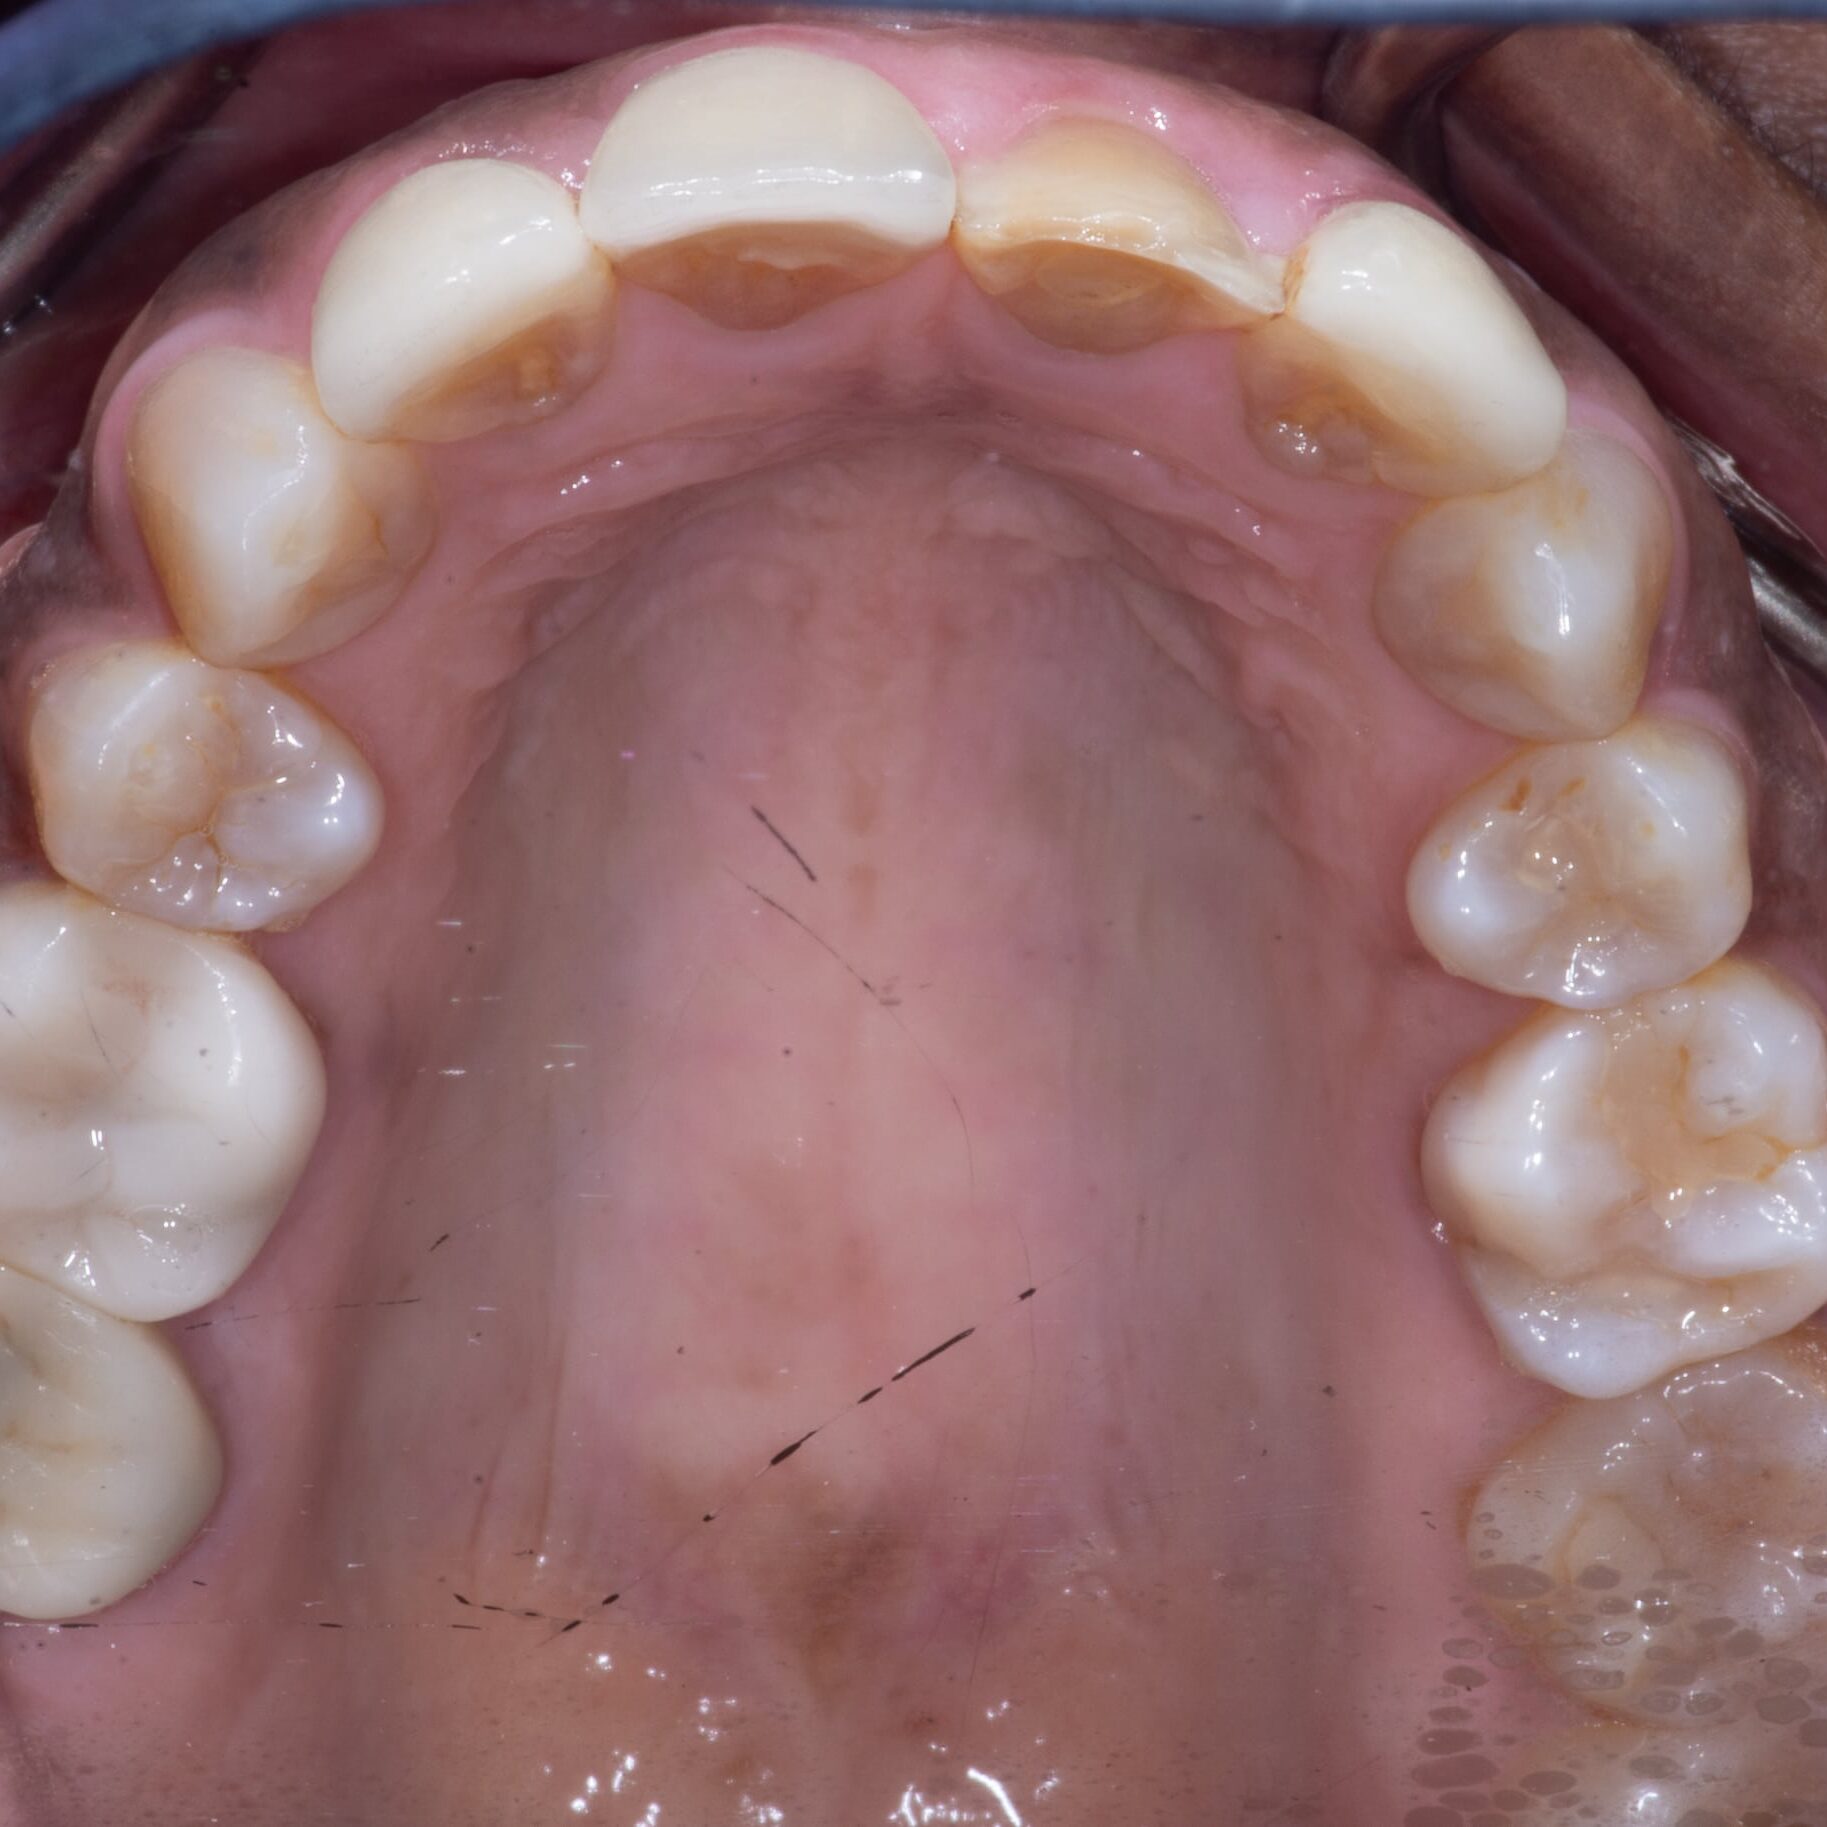

Step 3

When the remaining veneers were removed, we were able to see just how much tooth structure had been removed to place the initial veneers.